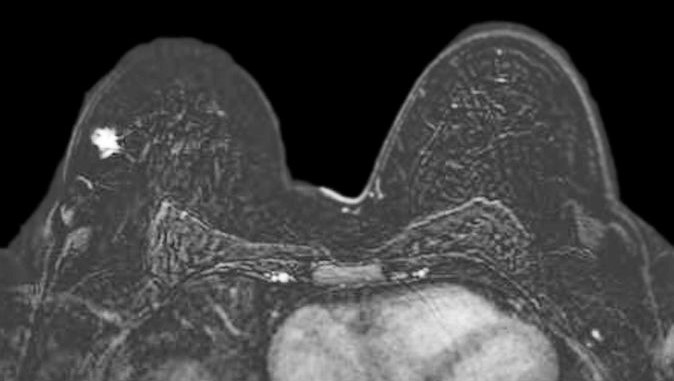

Breast MRI demonstrating breast cancer

PRI's breast imaging specialists bring decades of experience in the management of both benign and malignant breast disease.  Our team is trained in the use of the most advanced breast imaging technology, including mammography, tomosynthesis, diagnostic mammography, breast MRI, and directed diagnostic ultrasound and whole breast screening ultrasound.